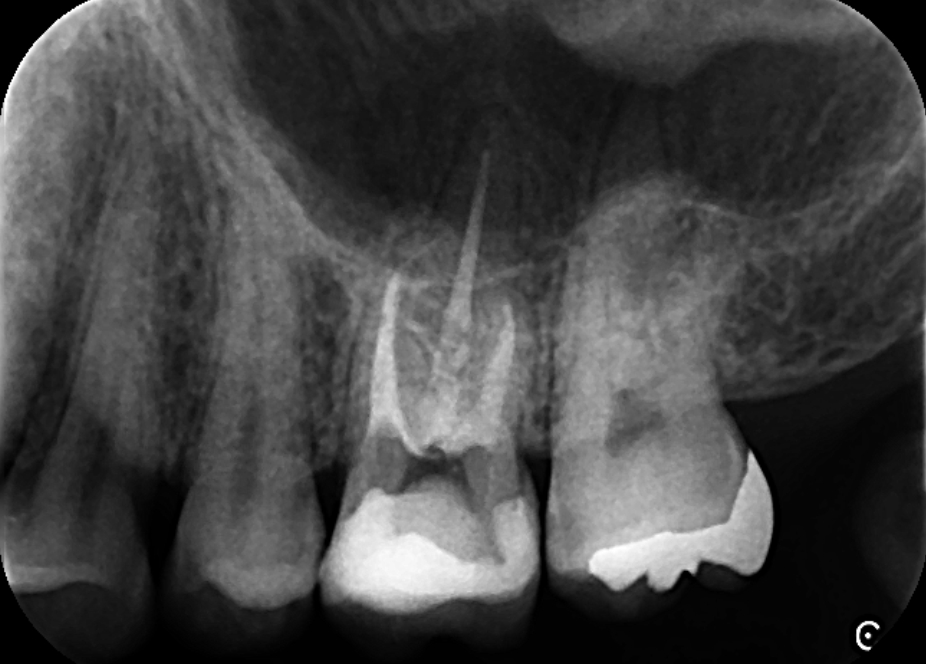

精密根管治療を行い根尖病変と上顎洞炎の改善をはかりました。画像は、根管充填時のレントゲン写真です。